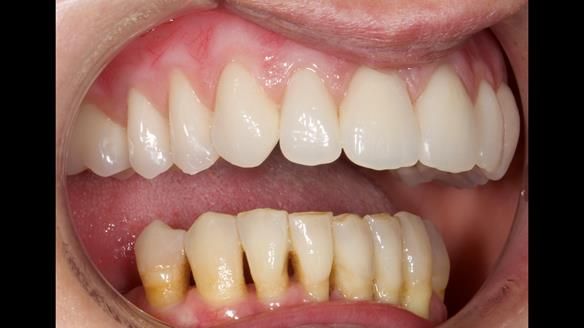

She had previously suffered from generalised periodontitis – stage IV, grade C, currently stable, with reduced attachment across the upper arch.

By the time she came to me, her periodontal condition was stable — but the aesthetics in the upper jaw were very poor.

We provided her with an immediate upper denture (Mk 1), followed by a definitive metal-based upper denture (Mk 2). A lower removable partial denture was discussed, to be made only if needed once the upper treatment was complete. However, at review, this wasn’t necessary — Adnana had excellent neuromuscular control and function, even with a shortened dental arch (SDA).

- Immediate denture (Mk 1) fitted the same day the teeth came out

- Definitive denture (Mk 2), metal-based and custom-designed for her face

- A restored smile, restored lip support, and a patient who owned the journey